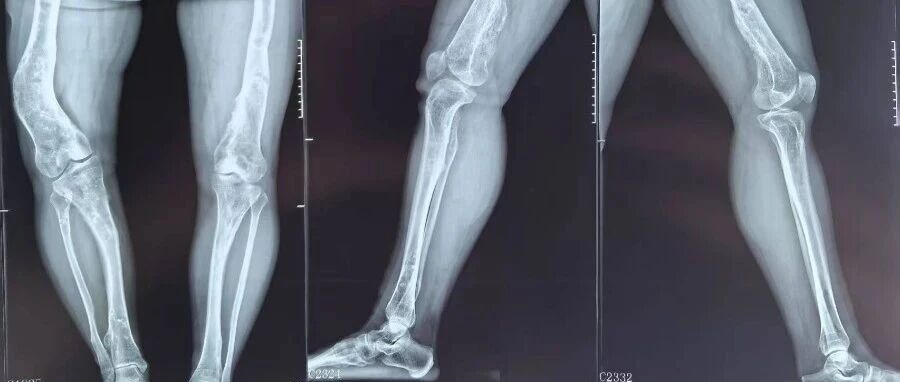

Different diseases requiredifferent treatments同病不同治最近,北京积水潭医院足踝外科主任武勇带领北京积水潭医院郑州医院(郑州市中心医院)足踝外科团队,完成了3台踝关节关节病手术。有意思的是,这三位患者都是因为“脚脖子”痛来的,但手术团队根据他们疼了多久、病变范围大小,还有个人身体情况,选了三种不一样的手术方式——这正是踝关节关节病阶梯治疗“规范、标准、......